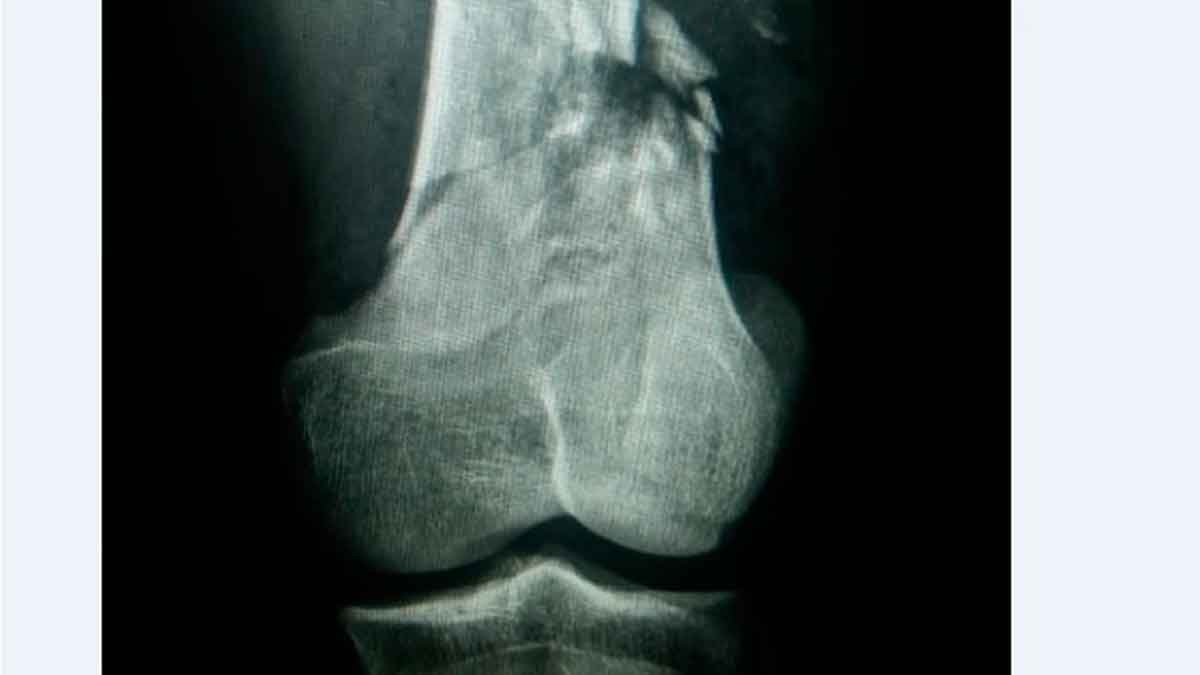

El herido fue identificado por la Policía como Luís Andrés Márquez, de 22 años, quien presenta lesiones de balas múltiples en las piernas con fractura en fémur izquierdo.